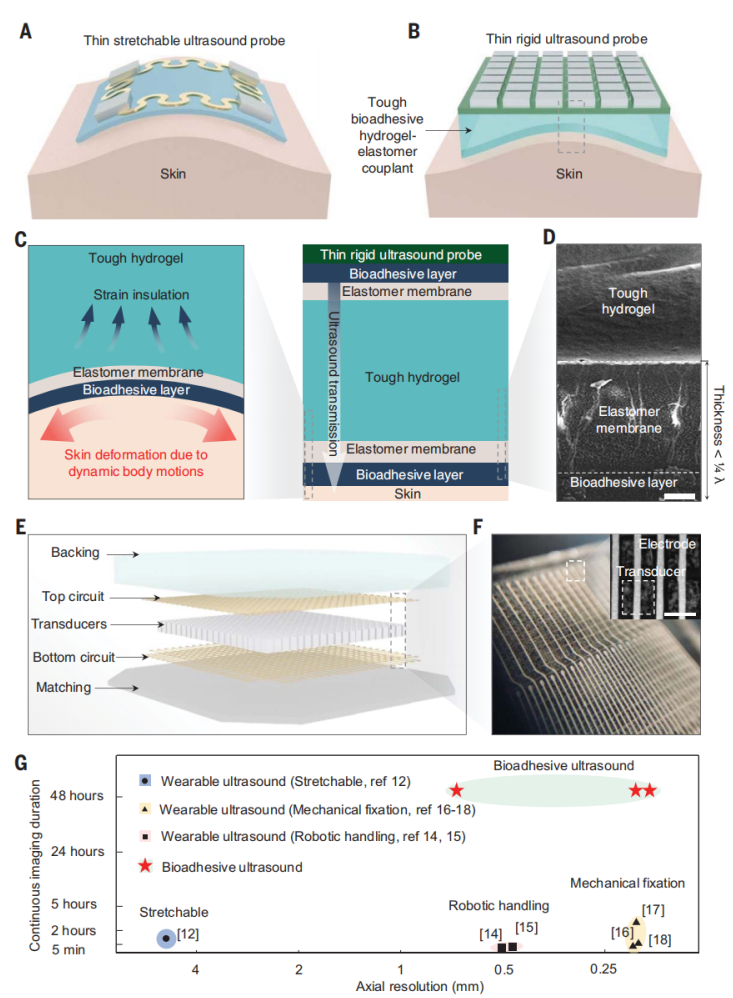

虽然可延展的超声成像设备在佩戴性方面得到了改善,但它仍然受到了诸多限制,包括低成像分辨率、身体运动期间不稳定的成像质量、连续成像时间短(1小时),易受装置故障影响。(连续成像持续时间被定义为设备可以附着或佩戴在皮肤上的最长时间。)这些限制主要来源于装置的设计问题,设备由可延展基板上的压电元件组成(图1A)。尽管可延展的基底可以随着皮肤一起变形,但是它限制了元件的密度(每平方厘米156个单元),并且与背衬层和匹配层不相容,导致成像分辨率低。另外,当基底在身体运动下随着皮肤变形时,元件的空间和角度位置发生了不可预测的变化,而这影响了设备的成像稳定性。

图1.BAUS装置的设计和成像性能

本文报告了一种生物粘附超声(BAUS)装置,该装置由一个薄且坚硬的超声探头组成,并通过一种柔软、坚韧、抗脱水材料制成的耦合剂层和生物粘附性水凝胶-弹性体混合物牢固地粘附在皮肤上(图1,B到D)。

BAUS探头有着高密度的元件(每平方厘米400个单元),这使得它在身体动态运动下具有稳定的元件位置,以及在长期应用中有着较高的可靠性。BAUS耦合剂能有效地传递声波,使BAUS探头免受皮肤变形的影响,并在48小时内保持牢固舒适的皮肤粘附力。

BAUS探头由中心频率为3、7或10MHz的高性能压电元件阵列组成(图1,E和F)。每个元件由BAUS探头的顶部和底部电路控制。这些电路可以通过三种技术制作:3D打印(图1F)、激光刻蚀和光刻,他们分别能达到100、10和1μm的电路线分辨率。同时,利用优化后的声学匹配层覆盖在底部线路上从而增强到皮肤的声波传递能力,将优化后的声学背衬层覆盖在顶部电路上来抑制共振效应。BAUS探头由一层环氧树脂密封,使其在长期应用中具有高稳定性和可靠性。本文还设计了一种即插即用的输入输出,并将其与柔性扁平电缆连接。BAUS探头的厚度为3mm,长度和宽度为1-2cm,重10-40g。

尽管 BAUS 探头的成像分辨率优于现有的可穿戴超声设备(图1G),未来可以进一步改进BAUS探头以获得更好的成像质量。

当前 BAUS 探头的间距相对较大(0.5 毫米),并且会产生栅瓣,尤其是在7MHz和10 MHz的BAUS 探头中。虽然通过使用平面波复合方法可以减轻栅瓣伪影,但将来 BAUS 探头的间距可以进一步减小来消除伪影。虽然目前的 BAUS 探头没有仰角聚焦,但可以将薄型 (<1 mm) 仰角透镜添加到将来的 BAUS 探头中用于仰角聚焦以获得更好的成像质量,尤其是对于深部器官的成像。